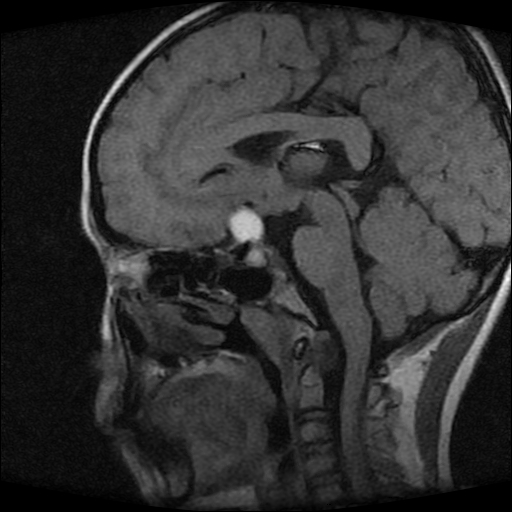

男性,12岁。反复头痛呕吐半月。脑积液无异常。病变部位ct值32hu,dwi无异常。

鞍上为主,累及鞍内,垂体受压位于鞍底。mri呈短t1、长t2信号,不太支持生殖细胞肿瘤,首考颅咽管瘤。

鞍内囊性占位性病变,t1wi、t2wi,均为高信号影。ct平扫为等密度。发病年龄较小。故首先考虑颅咽管瘤,可以做ct增强扫描